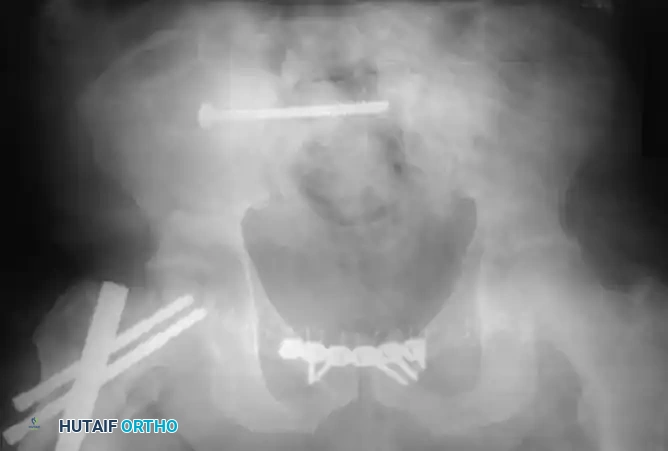

1. Iliosacral Screw Fixation

For sacral fractures and sacroiliac joint disruptions, fluoroscopically-directed percutaneous iliosacral screw fixation is the workhorse technique. Screws are passed from the outer table of the ilium, across the SI joint, and into the dense bone of the sacral body (S1 and occasionally S2).

Fluoroscopic Positioning:

Safe placement requires an intimate understanding of upper sacral anatomy and flawless radiographic technique. Graves and Routt quantified the exact sagittal plane tilt of the fluoroscope required to obtain true inlet and outlet views:

- Ideal Inlet View: Average tilt of 25 degrees.

- Ideal Outlet View: Average tilt of 42 degrees.

Complications of IS Screws:

- Neurological Injury: There is a high risk of iatrogenic damage to the L5 nerve root (anterior to the sacral ala) and the S1 nerve root (within the sacral foramina). Because neurological injury occurs in up to 30% of transforaminal sacral fractures (Denis Zone II), some surgeons advocate for open reduction and direct decompression of the neural foramina prior to fixation.

- Biomechanical Failure: Griffin et al. demonstrated a high failure rate (13%) when percutaneous iliosacral screws were used in isolation for vertical shear fractures through the sacrum.